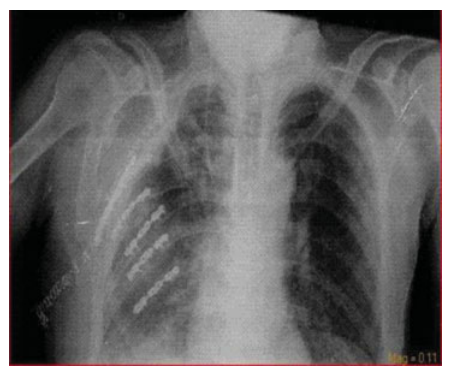

因此,向患者胸腔内置入32号胸腔管进行胸腔引流,并将其送至重症监护室进行后续治疗。患者在72小时后因呼吸衰竭进行气管插管,尽管引流管已无液体和气体排出,但由于第14天仍需机械通气,计划对其进行外科稳定手术。右侧高位后外侧开胸切口显示第2至第7根肋骨骨折,其中部分为压迫胸腔的粉碎性骨折。对所有骨折线均进行去骨膜处理,胸壁稳定手术使用钛重建板和螺钉完成(Biomet Microfixations, Jacksonville, Florida, United States)(►图3)。患者在术后第3天拔管,术后第8天一般情况良好,生命体征稳定,予以出院(共计22天)(►图4)。

图4. 患者术后胸片。